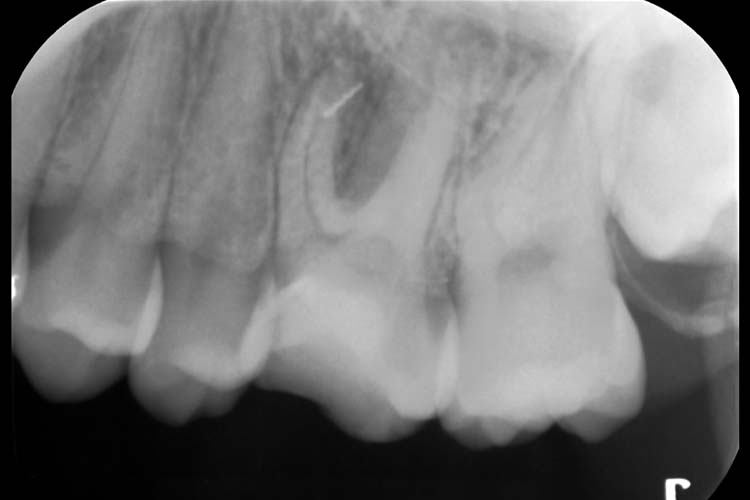

症例4

BEFORE

AFTER

| 患者 | 20代 女性 |

|---|---|

| 主訴 | 左上の歯が痛い。 |

| 治療期間 | 6回 約2ヶ月 |

| 治療費 | 保険診療 |

| 治療内容 | 保険診療による精密根管治療、ファイル破折除去 |

| 治療のリスク | 破折ファイルが取れない可能性、破折ファイルを取るために根管内歯質を多少削る必要があります。 |

詳細を見る